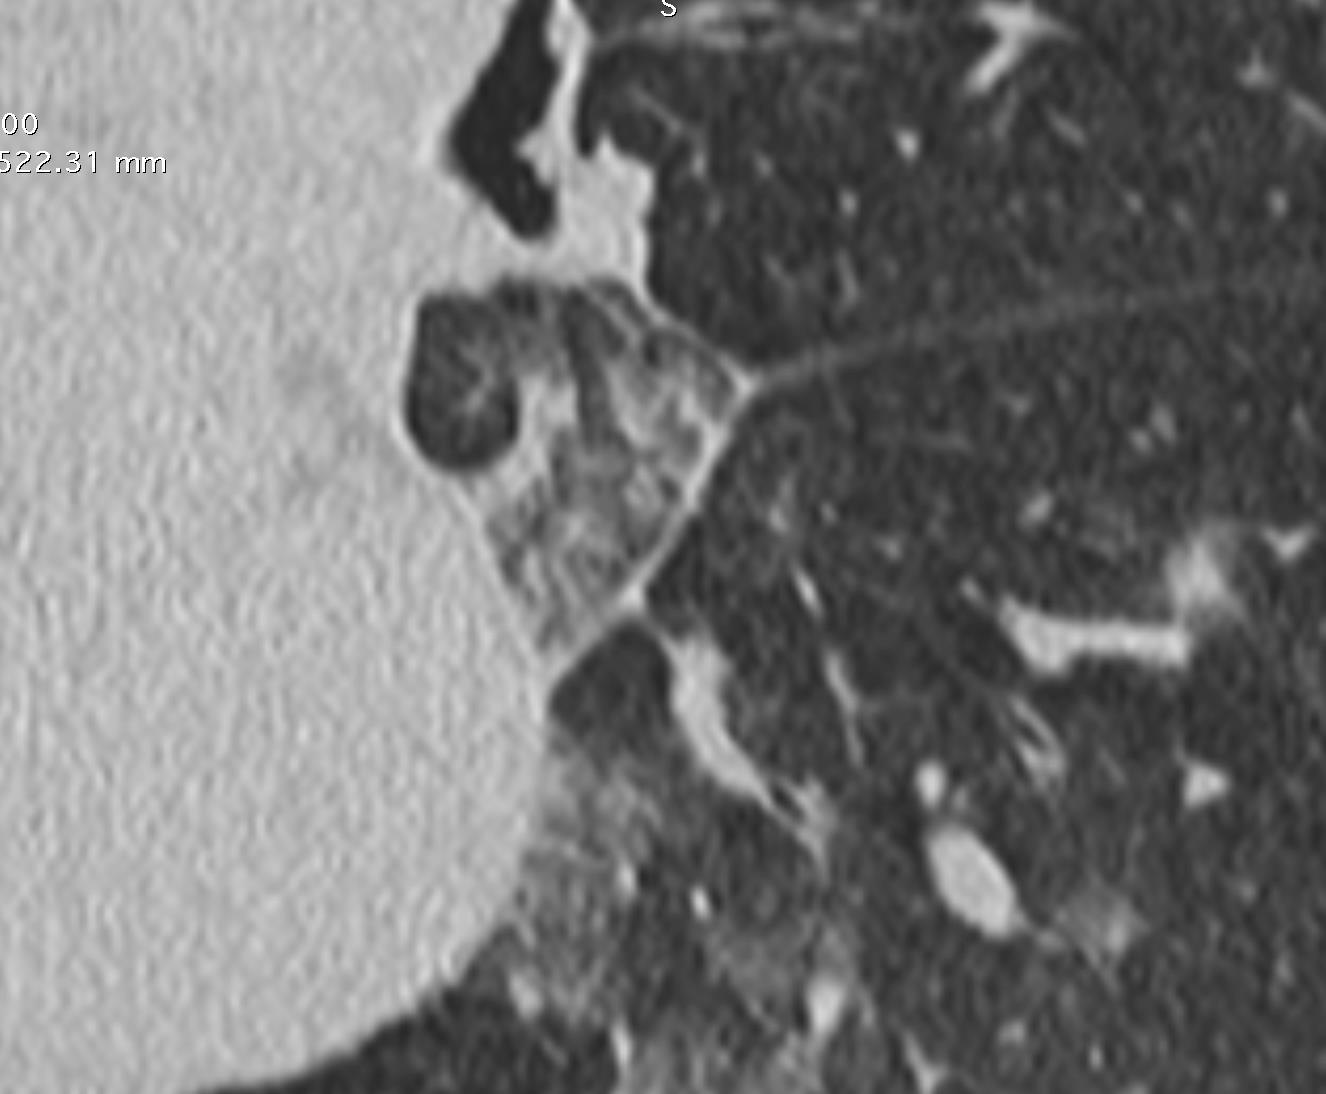

Imaging of Covid 19 infection in children COVID 19 Late

Late

37